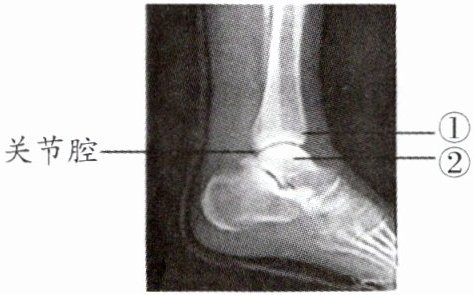

3. 下图为某人左脚的踝关节射线透视图像,①②表示踝关节内的结构。下列说法

A.①是关节头,②是关节窝

B.①②表面覆盖着关节软骨

C.关节腔内有滑液,使关节灵活

D.踝关节在运动中起枢纽(支点)作用

正确的是(A

)A.①是关节头,②是关节窝

3. A